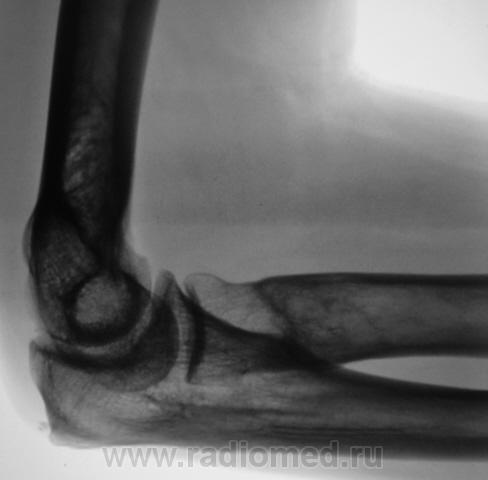

Представленное ниже (желтые стрелки), можно рассматривать как вариант развития (нормы), или как-то по- другому?

на мой взгляд что-то есть. вздутие прокимальной трети лучевой кости с истончением кортикального слоя, остеопороз. какая то костная киста. нужна другая сторона, клиника. недалеко до патологического перелома.

Кист не видно, вероятно такая глубокая шейка луча...

А не было ли тут перелома шейки лучевой кости?

Я думаю, что это, все-таки, вариант развития. Посмотрите вот здесь http://radiographia.ru/node/1393 , я там выкладывала два подобных случая у детей, тоже мне тогда не понятных. Пришла к выводу, что это вариант развития.

Может все таки что та давит со стороны локтевой кости, давит давно и долго - вот тогда это будет аррозия - атрофия от давления...Как Вы думаете?

Вряд ли так может давить, это не похоже на атрофию от давления.

Да, высказывались. Но ничего того, что могло вызвать атрофию от давления, выявлено не было, и жалоб никаких нет.